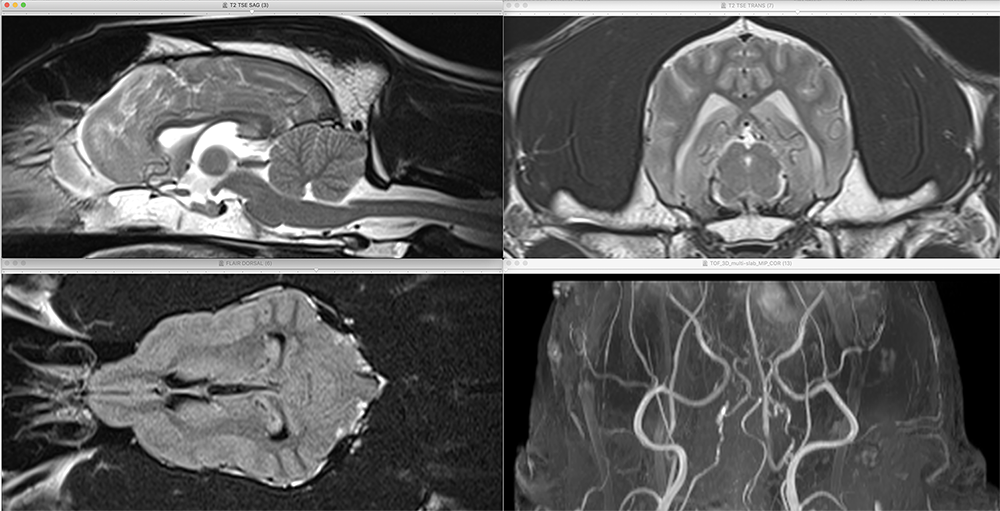

- Travail en groupe : Résolution de cas cliniques variés à l'aide de vidéos et d'imagerie médicale